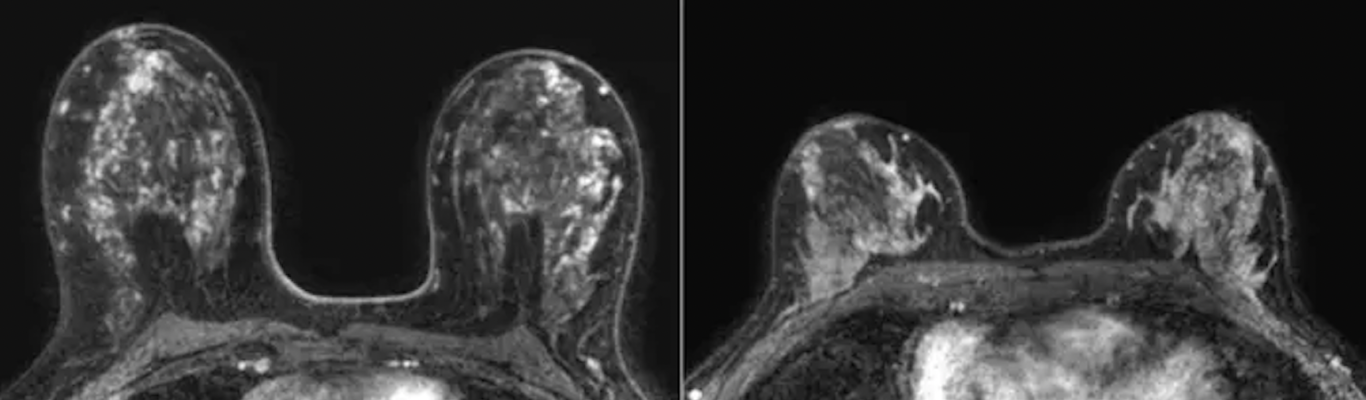

Representative transverse dynamic contrast-enhanced MRI scans in patients in the low and high tertiles of volume of enhancing parenchyma. Please note differences in high and low volumes of enhancing parenchyma are not visible to the naked eye on MRI scans. Left: Baseline MRI scan in a 50-year-old woman with a body mass index (BMI) of 23 and marked background parenchymal enhancement (BPE) who was stratified into the high tertile of volume of enhancing parenchyma. Cancer was detected with MRI in the second screening round. Right: Baseline MRI scan in a 51-year-old woman with a BMI of 24 and marked BPE who was stratified into the low tertile of volume of enhancing parenchyma. No cancer was detected during 6 years of follow-up. Image courtesy of RSNA.Br

After adjusting for age, BMI and BPE, the researchers found that breast cancer occurrence was greater in women with higher volumes of enhancing parenchyma compared to women with low volumes of enhancing parenchyma.